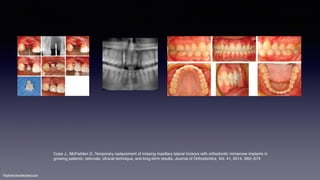

Cope J., McFadden D.,Temporary replacement of missing maxillary lateral incisors with orthodontic miniscrew implants in

growing patients: rationale, clinical technique, and long-term results, Journal of Orthodontics, Vol. 41, 2014, S62–S74